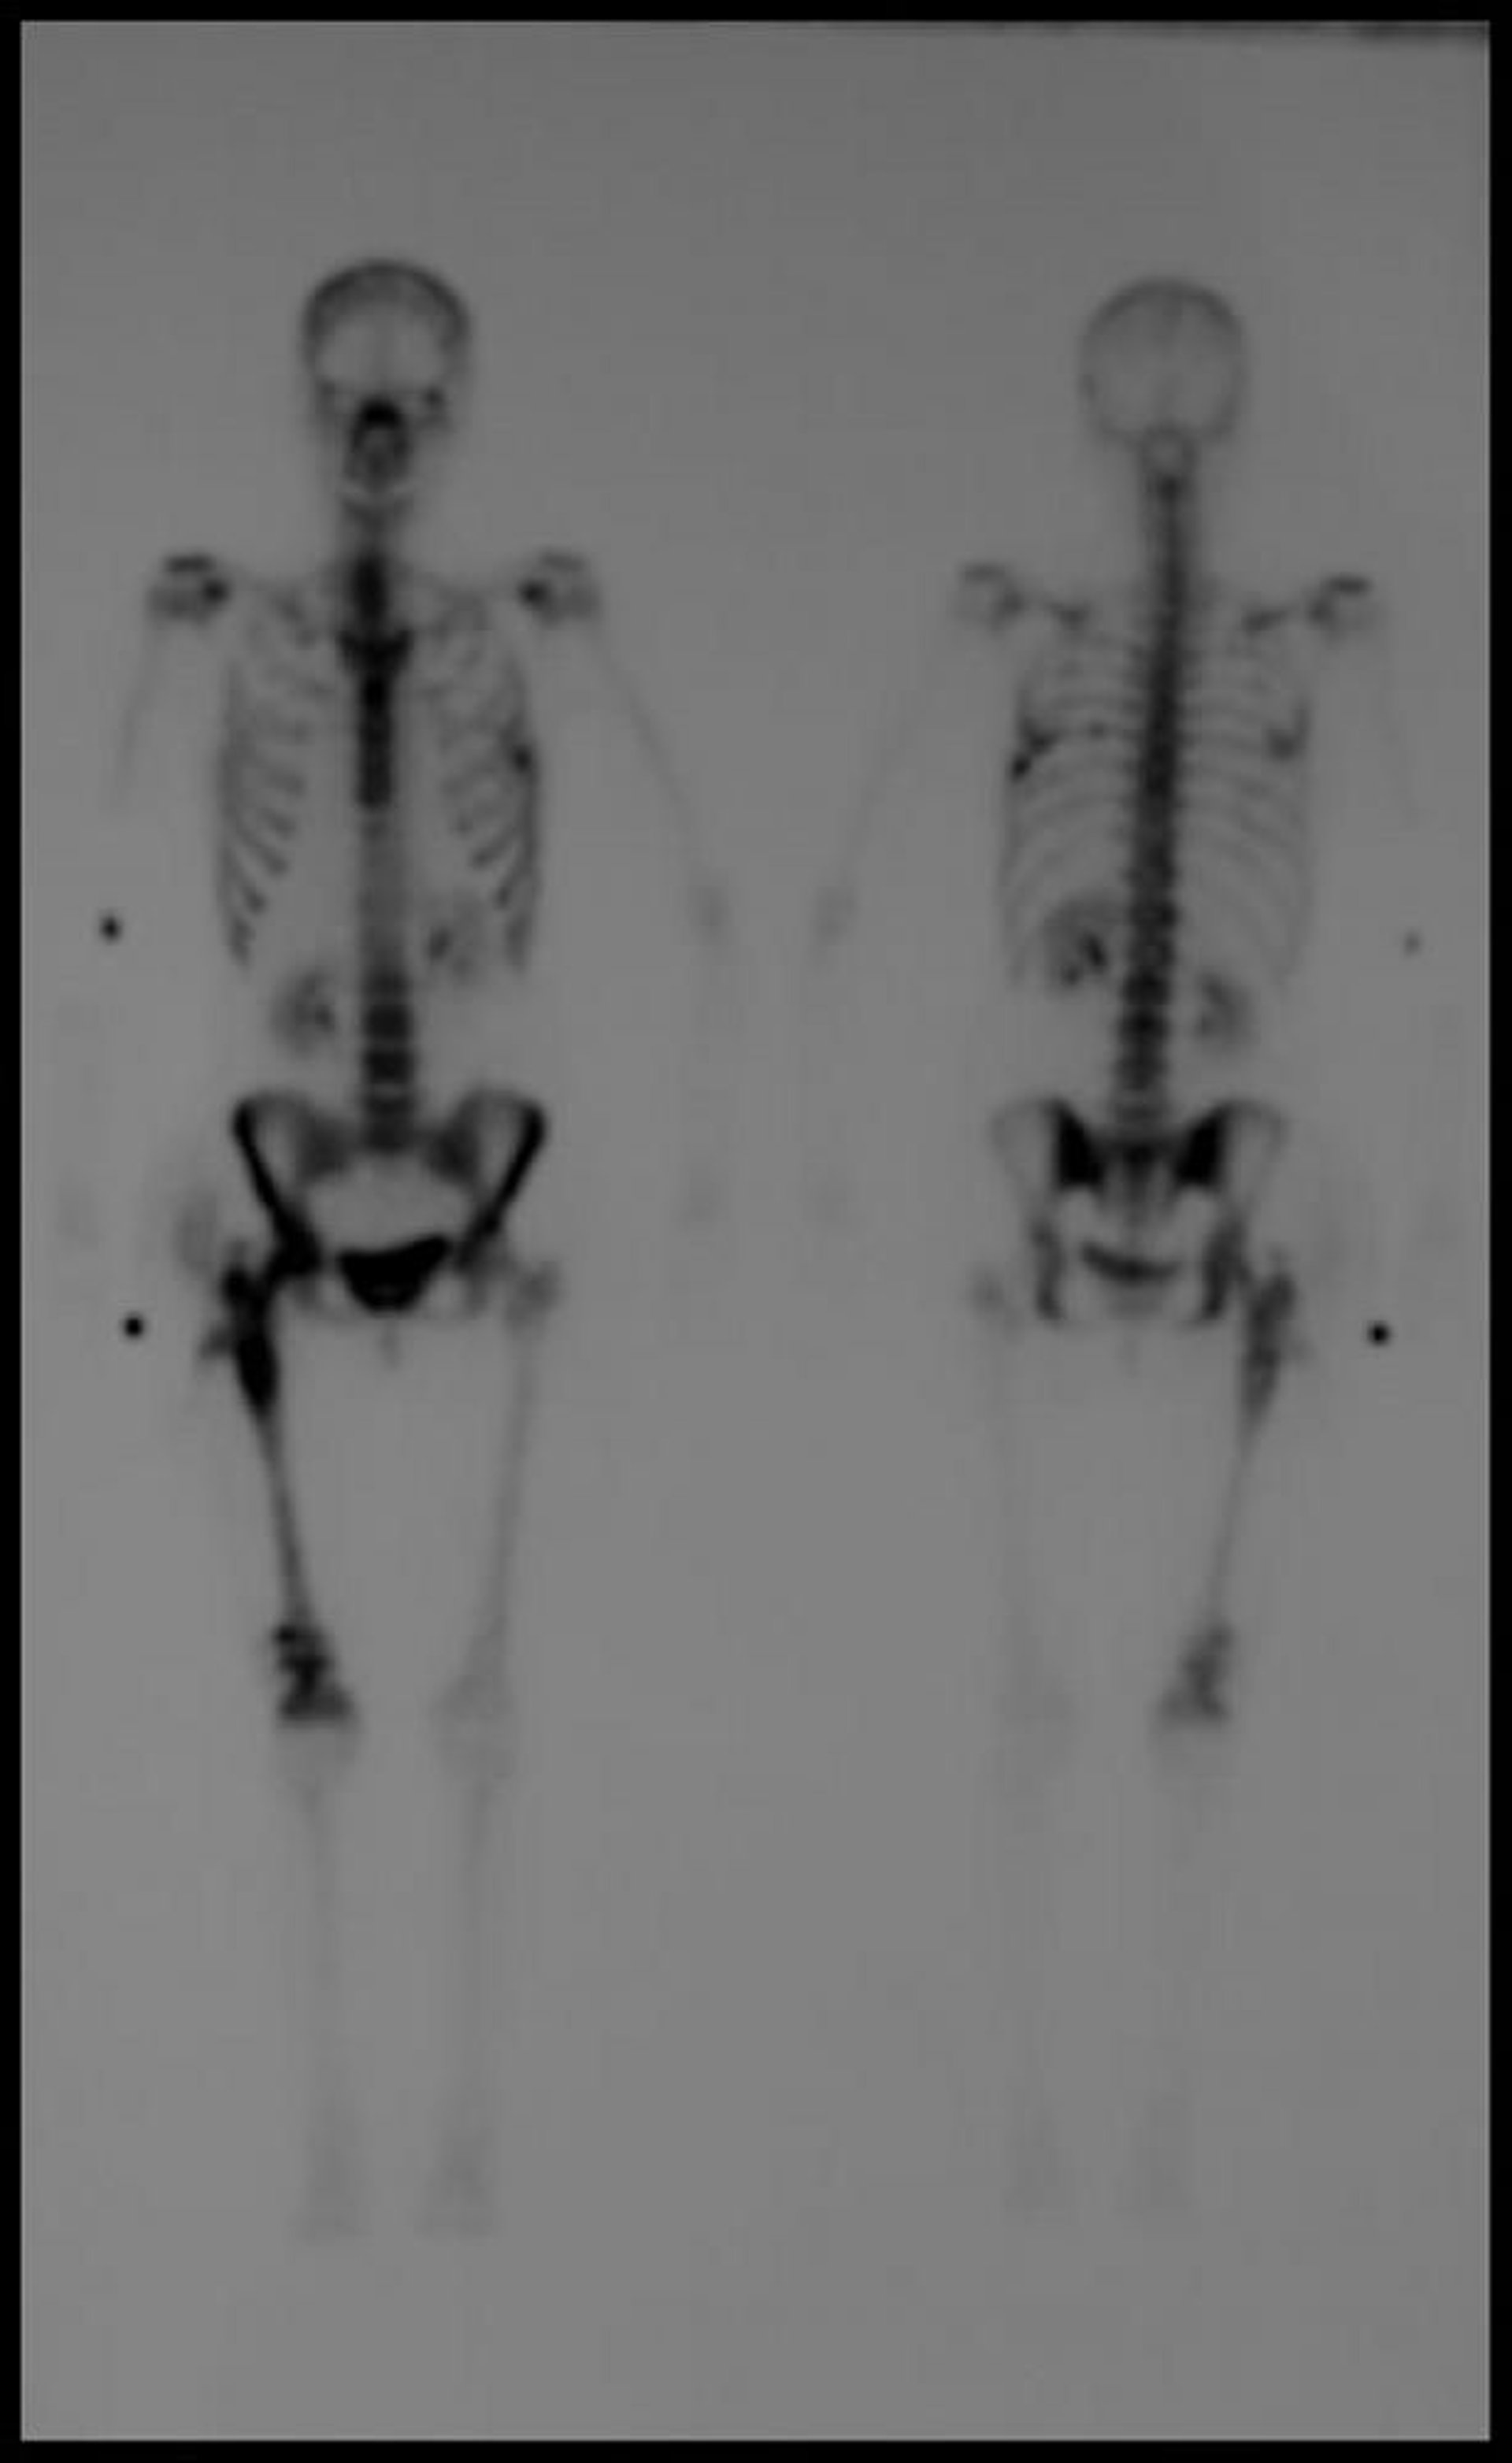

Cintilografia óssea de corpo inteiro

A imagem cintilográfica óssea tardia com tecnécio-99m de corpo inteiro mostra múltiplos focos de aumento da captação de contraste sugestivos de doença metastática.

Imagem cedida por cortesia de Hakan Ilaslan, MD.